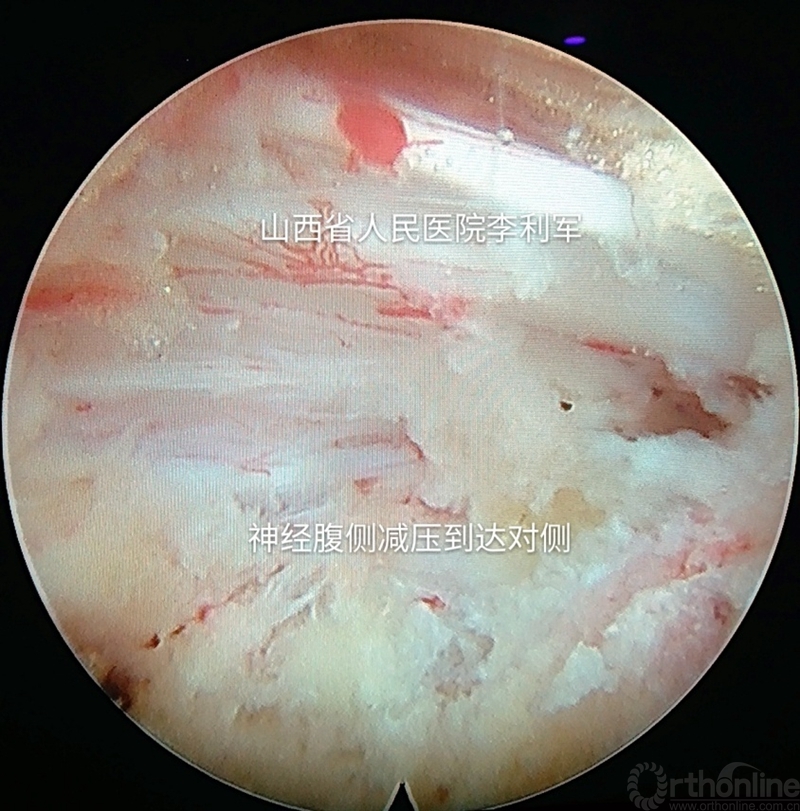

第四步:逐步推进通道,用镜下工具逐步行神经腹侧的全程减压,达到过中线或对侧,根据需要可以再重复以上过程再次行镜下椎间孔扩大成型。如图8-9

图8 逐步推进通道行腹侧全程减压

图9 逐步推进通道行腹侧全程减压